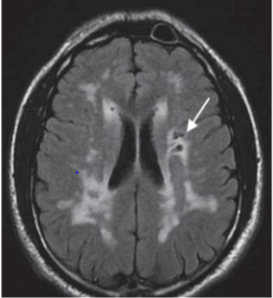

A mutation in this gene leads to an autosomal dominant condition that mimics CNS vasculitis, causing recurrent subcortical strokes and T2 white matter hyperintensities in a young patient (40s-50s),

What is NOTCH3.